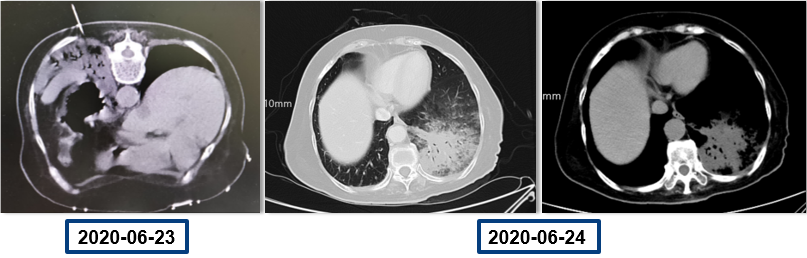

为提升肺癌前线免疫联合抗血管治疗的诊疗观念,学习与追踪肺癌领域诊疗最前沿知识,充分交流免疫/抗血管用药不良反应管理临床经验,【An例说】肺癌病例项目,征集大量临床高质量免疫联合抗血管治疗肺癌病例,并邀请全国各区域中青年及高职称医生与顶级TOP KOL互动发声!通过理念结合实践,研究结合病例,线上联动,共同促进学术由KOL/ROL向中青年医生下沉,为提升我国肺癌诊疗整体水平势在必行。免疫治疗的出现,对于晚期肺癌患者而言,显著提高了患者的生存质量及延长生存期,多项研究表明免疫治疗对于PD-L1表达阴性的患者也具有一定的治疗效果。为此,上海长海医院(海军军医大学第一附属医院)团队为您带来一例肺癌免疫联合抗血管病例分享。 患者,女性,78岁 2017年体检时发现左下肺结节,未行诊断及治疗。 2018.11.21、2019.09.24胸部CT均提示病灶较前变大,仍未诊治。 影像学检查 2020.01初逐渐出现胸闷、气短,活动后尤为明显。多次就诊于当地医院输液治疗(具体不详)。入院前2周胸闷,气急症状加重,无发热,无明显咳嗽,咳痰。2020.06.23入院。 影像学检查 既往史:高血压病30余年,最高血压170/90mmHg,规律服用美托洛尔12.5mg+利血平 0.1mg/日,自诉血压控制可。 个人史:无特殊 婚育史:无特殊 家族史:无特殊 T:37.0℃ P:104次/分 R:30次/分 BP:134/58mmHg 右肺及左肺可闻及湿罗音,左下肺呼吸音弱,无胸膜摩擦音。 心脏查体无异常。 入院后 CT引导下肺穿刺 穿刺后无咳嗽咯血,胸闷气急症状无加重。 6.25 出院等病理。 自行口服易瑞沙治疗,家中持续吸氧。 出院后3天突发病情变化: 6.28 凌晨1点左右,如厕后出现呼吸困难加重,晕倒。家属约2点发现,送至急诊,急诊予化痰、平喘、抗感染等对症治疗。 影像学检查 急诊检验检查: 【血气分析】PH 7.35、PO2 45.9mmHg、PCO2 62.6mmHg 【BNP】23.38pg/ml;【D-二聚体】0.32 【血常规】WBC:9.23×109/L、RBC:3.58×1012/L、HGB:98g/L、N%:80.2%、PLT:203×109/L。 【炎症指标】CRP:2.95mg/L;ESR:4mm/H;PCT:0.045ng/ml 【心电图】1. 窦性心动过速、2. ST-T异常。 血气分析 2020.06.29再次入院:左下肺腺癌、Ⅱ型呼吸衰竭、右肺阴影待查。 右肺渗出原因分析:感染?肿瘤进展?药物相关? 血常规变化: 选择治疗方案: 1. 两肺炎症,纵隔稍大淋巴结,炎症较2020.6.24进展,建议抗炎治疗后复查; 2. 左侧胸腔少许积液; 3. 两肺肺气肿、肺大泡,右肺中叶钙化灶; 4. 右侧第4肋骨皮质扭曲,请结合临床; 5. 甲状腺两侧结节,请结合超声。 右下肺腺癌 PD-L1无表达 抗血管生成与免疫联合的优点: 1、抗血管生成,靶点全面、强效抑制 2、抑制肿瘤细胞增殖和迁移,重塑肿瘤微环境,联合增效 3、肿瘤血管正常化及重塑,减轻免疫抑制状态 4、增加免疫效应细胞浸润 5、免疫刺激作用,激活免疫效应细胞 信迪利单抗联合安罗替尼的临床研究:这是一项前瞻性、非随机、三臂、Ib期临床研究。 临床研究试验设计 临床研究PFS和OS曲线 安罗替尼联合信迪利单抗一线治疗NSCLC,ORR达72.7%,DCR达100%,mPFS=15.6m,24m,OS率83.9%,表现出良好的治疗潜力。 派安普利单抗联合安罗替尼的临床研究:随机、双盲、多中心III期临床研究(NCT03866980) 临床研究试验设计 安尼可联合安罗疗效的ORR和DCR分析 数据截止日期:2021.1.13,共26例患者入组安尼可联合安罗替尼组,21例患者至少完成一次疗效评价。 帕博利珠单抗+安罗替尼 8mg。 治疗过程影像学检查 疗效评估: 2021.08.03: 疗效评估PR,截止目前PFS=15m。 该病例采用PD-L1抑制剂帕博利珠单抗联合小分子多靶点抗血管生成药物安罗替尼治疗老年肺腺癌患者,获得了15个月的PFS,提示对于驱动基因阴性,PD-L1无表达的晚期非小细胞肺癌患者免疫联合抗血管生成药物治疗是NSCLC患者一线治疗的选择和手段之一。 Impower150研究显示,贝伐珠单抗联合PD-L1抑制剂阿替利珠单抗+化疗显著改善了无突变非鳞NSCLC患者的PFS,中位OS达19.4个月(对照组14.7个月),ORR为71%。但治疗相关的毒副反应较大,一定程度上影响患者生活质量。小分子TKI联合免疫作为肿瘤去化疗联合治疗模式,越来越受到关注,前期探索性前瞻性随机临床研究包括信迪利单抗+安罗替尼(ACTION研究)、派安普利单抗+安罗替尼(AK105-301研究)和卡瑞利珠单抗+Apatinib/ target=_blank class=infotextkey>阿帕替尼(SHR-1210-III-315 研究)等一线治疗驱动基因阴性晚期NSCLC均得到了较好结果, 信迪利单抗联合安罗替尼组ORR达72%,DCR100%,中位PFS15.6个月,2年OS率83.9%,耐受性良好,显示出多靶点抗血管生成药物联合的良好应用前景。 免疫与抗血管生成药物以及与其他药物或方式联合该如何排兵布阵,肺癌治疗如何真正践行个体化和精准化,还有许多问题和挑战,有待进一步研究拓展和证实。 病例分享 焦洋 教授 上海长海医院,副主任医师,副教授 海军军医大学长海医院呼吸与危重症医学科 美国田纳西州大学附属医院呼吸与危重症医学科访问学者 上海市医学会呼吸分会感染学组秘书 中国老年医学会感染诊治与合理用药学术委员会委员 专业方向:疑难、复杂肺部感染及呼吸危重症的救治,肺癌的早期诊断和治疗。 专家点评 韩一平 教授 海军军医大学第一附属医院 呼吸与危重症医学科教授、主任医师 博士生导师 海军军医大学第一附属医院临床教育中心主任 中华医学会呼吸分会肺癌学组委员 中国医药教育协会肺部肿瘤专委会常委 中国医师协会全科分会委员,上海全科分会副会长 《中国肿瘤生物治疗杂志》《中国全科医学杂志》 《第二军医大学学报》《内科年鉴》等编委 获校“特级优秀教师”,上海市“育才奖” 首届上海“最美女医生” 主编发表教材或专著5部,近年发表文论50余篇 *仅供医学药学专业人士阅读 文章来源:ONCO前沿案例详情